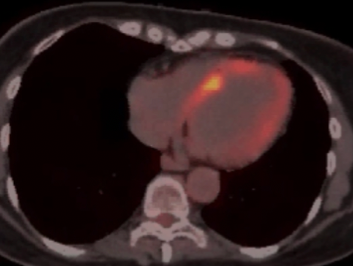

Granulomatous Cardiomyopathy